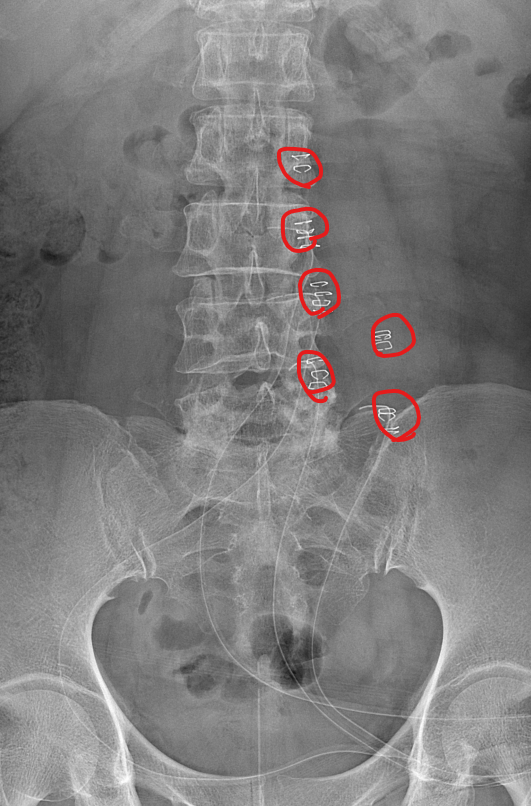

척추관 협착증은 척추관이 좁아지거나 협착되어 척수나 신경근을 압박하는 상태를 말합니다. 이런 경우, 양방향 척추 내시경이 매우 유용한 치료 수단이 될 수 있습니다.

- 계획: 양방향 척추 내시경은 미세한 카메라와 도구를 사용하여 척수와 주변 신경 구조를 정밀하게 시각화할 수 있습니다. 이를 통해 정확한 진단을 내릴 수 있으며, 각 환자에게 맞는 개별적인 수술 계획을 수립할 수 있습니다.

양방향 척추 내시경은 척추관 협착증과 같은 척추 질환의 치료에 있어서 현대적이고 효과적인 접근법 중 하나로 인정받고 있습니다.